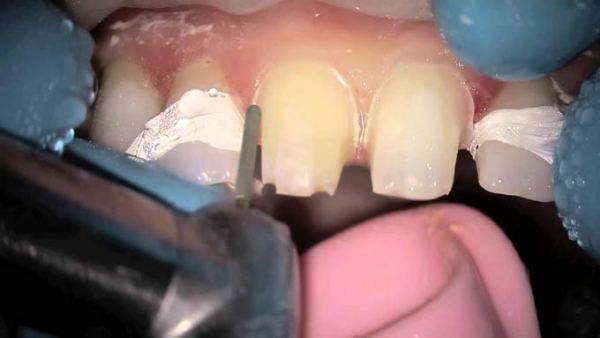

- Непосредственное препарирование – в зависимости от цели, способы обработки зуба будут отличаться между собой. Так, если стачивают жевательную единицу, то воздействуют на верхние бугорки. А при обработке резцов нужны разнонаправленные движения.

Передние зубы стачивают алмазным бором в том случае, если они значительно выступают. В более тяжелых обстоятельствах, сначала создается диагностический макет зубных рядов, и уже после досконального обследования их подпиливают.

Так, при обработке жевательных моляров стоматолог осуществляет аккуратное сошлифовывание верхнего слоя эмали с поверхности бугорков. При спиливании передних резцов осуществляются разнонаправленные движения.

Полученный гипсовый образец подвергается тщательному осмотру и оценочному подпиливанию. В качестве инструментария для проведения операции применяются карборундовые фрезы либо алмазные боры.

Перед тем как подпилить передние зубы, врач сначала определяет проблемные участки, а также оценивает состояние эмали. Выявить неровности зубных рядов можно при помощи копировальной бумаги, восковой пластины или жидкого аэрозоля. Проблемные участки окрашиваются в более интенсивный цвет.

Зубы, которые сильно выступают, подпиливают при помощи алмазного бора. В тяжелых случаях сначала изготавливают диагностические модели зубных рядов. После оценки их состояния производят диагностическое шлифование.